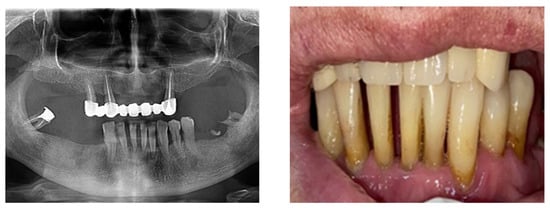

According to the SDCEP guidelines, when teeth have either over-erupted or drifted due to periodontal disease, it is recommended to check for fremitus or occlusal interference (Figure 4).

Figure 4.

Clinical and paraclinical aspects of dental mobility. (a) Paraclinical aspects of dental mobility; (b) Clinical aspects of dental mobility.